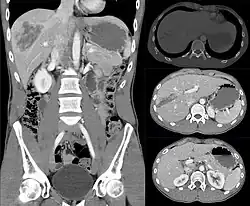

Imaging, such as the use of ultrasound or a computed tomography scan, is the generally preferred way of diagnosis as it is more accurate and is sensitive to bleeding, however; due to logistics this is not always possible.[6] For a person who is hemodynamically unstable a focused assessment with sonography for trauma (FAST) scan may take place which is used to find free floating fluid in the right upper quadrant and left lower quadrant of the abdomen. The FAST scan however may not be indicated in those who are obese and those with subcutaneous emphysema.[7] Its speed and sensitivity to injuries resulting in 400mL of free-floating fluid make it a valuable tool in the evaluation of unstable persons. Computed tomography is another diagnostic study which can be performed, but typically is only used in those who are hemodynamically stable.[7] A physical examination may be used but is typically inaccurate in blunt trauma, unlike in penetrating trauma where the trajectory the projectile took can be followed digitally.[8] A diagnostic peritoneal lavage (DPL) may also be utilized but has limited application as it is hard to determine the origin of the bleeding.[9] A diagnostic peritoneal lavage is generally discouraged when FAST is available as it is invasive and non-specific.[7]

Calculators have been developed that facilitate grading of liver injury based on imaging findings.[12]